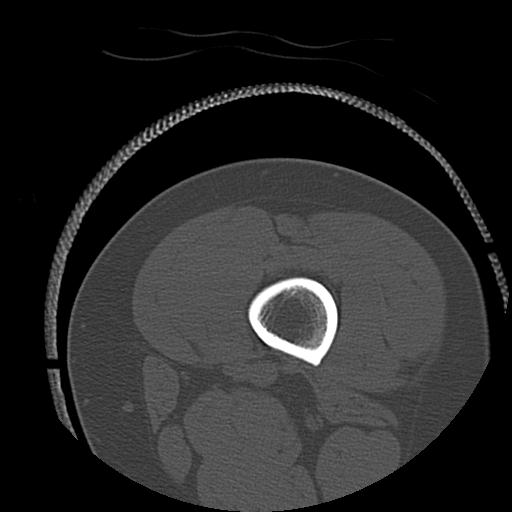

56476 8/28 4R 1/21 2R 左足関節 デジカメ写真 72歳女性 右足関節AS